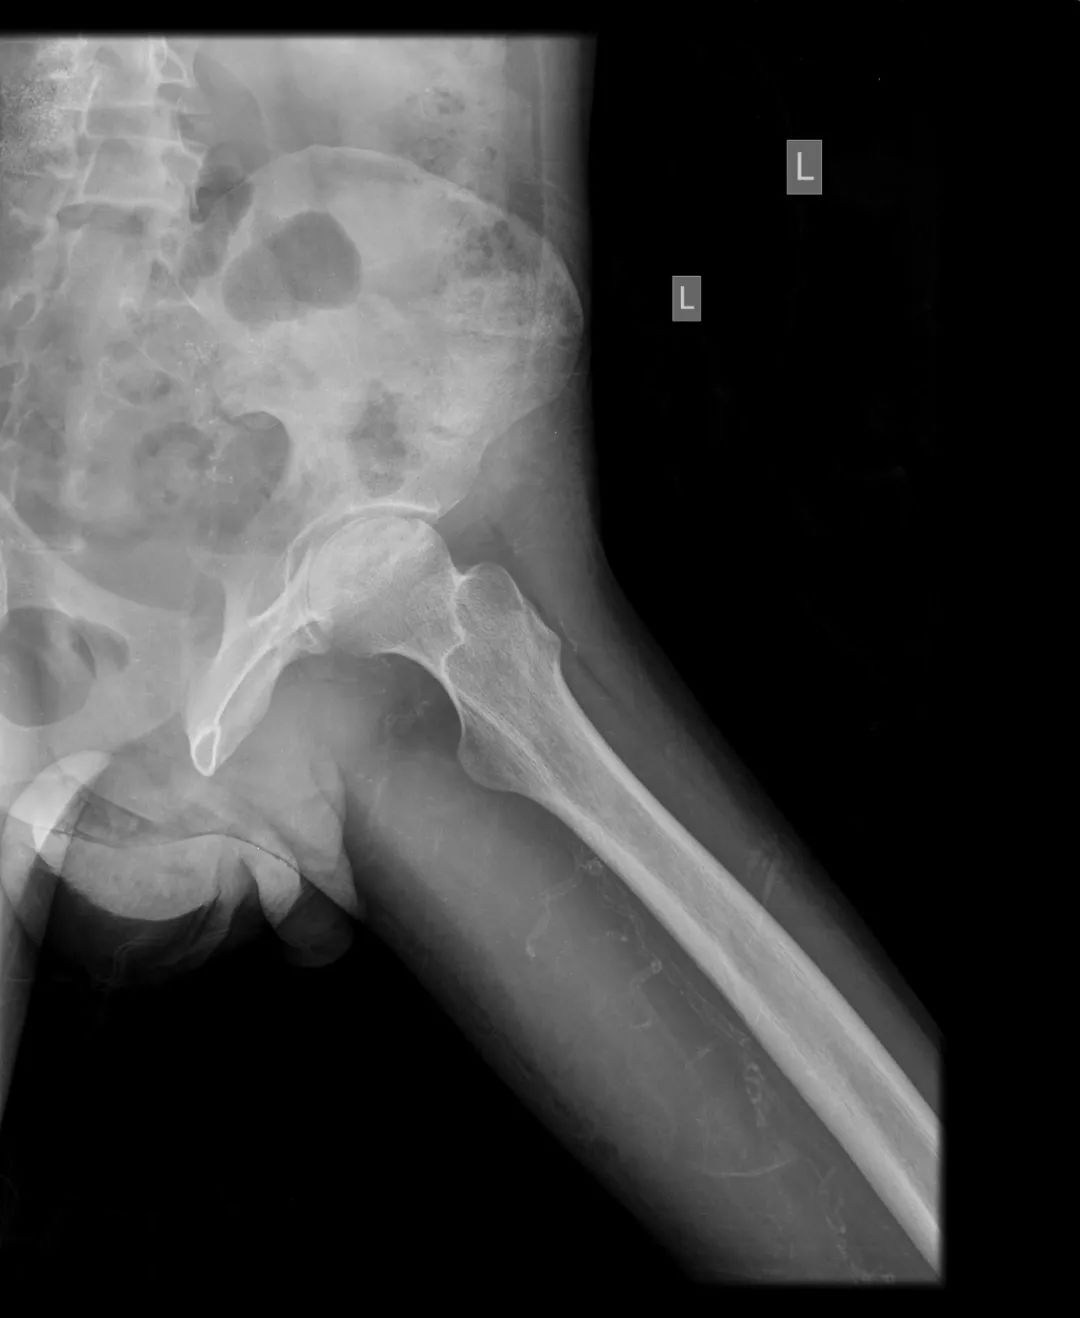

CASE M25 年轻男性,已知有类固醇治疗狼疮性肾炎史。伴有双侧髋关节疼痛和运动困难的抱怨。

不规则的透光区,代表软骨下囊变,与边缘硬化在两个股骨头。双股骨头呈线性软骨下骨折/断裂,伴有轻度塌陷/扁平。这些发现代表了双侧股骨头缺血性坏死。

这是典型的双边缺血性坏死有特征性的X线和MRI表现。患者有SLE合并狼疮性肾炎并接受类固醇治疗,均易发生AVN。